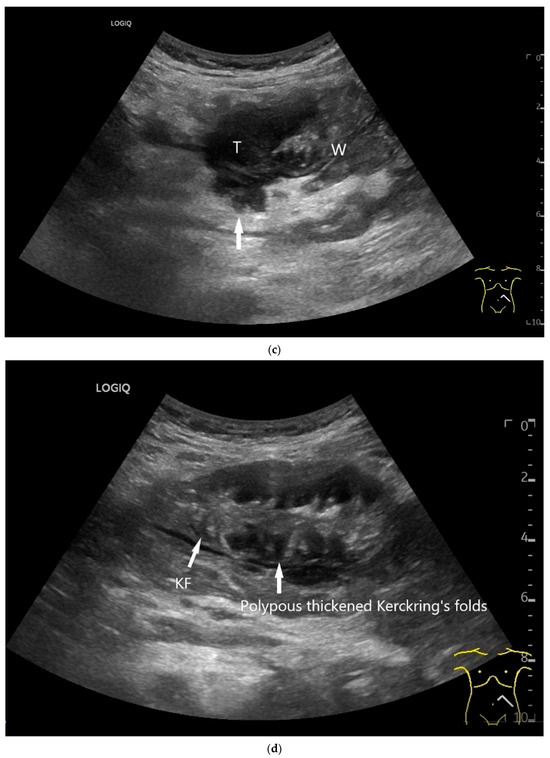

Figure 9.

Burkitt-Lymphoma. In a patient with weight loss, increased abdominal circumference, anemia, and physical weakness, the initial sonographic examination reveals an extensive tumor with intense hypoechogenicity and a connection to the jejunum in the left mid-abdomen. Despite its pronounced hypoechogenicity, a feeding vessel on CDI indicates a solid character (a). The tumor significantly thickens the wall and is intensely hypoechoic. The arrows point to the multisegmental hypoechoic wall thickenings (b). Normal wall structures are still visible (W), and the tumor extends beyond the wall (arrow) (c). In addition to delicate Kerckring folds (KF), there are significantly polypoid thickened KF with pronounced hypoechogenicity (d). The thickening of KF is very extensive (e). Wall thickening was found also in the stomach and colon and allowed endoscopic biopsy to establish the diagnosis.